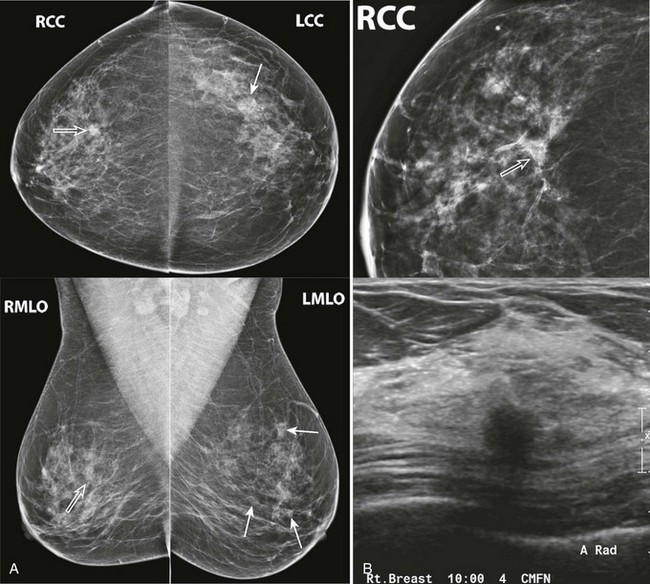

FIGURE 8-4 Metastatic Lesions in the Breasts.

This 47-year-old woman presented with a palpable lump in the right breast (marker). There are multiple circumscribed masses in both breasts. Note that the masses are primarily located in the retromammary fat and even in the axillary fat. US shows a solid hypoechoic mass with microloculated margins. Ultrasound-guided core biopsy samples were black in appearance. The patient subsequently gave a history of ocular melanoma 5 years earlier. Biopsy showed metastatic melanoma.